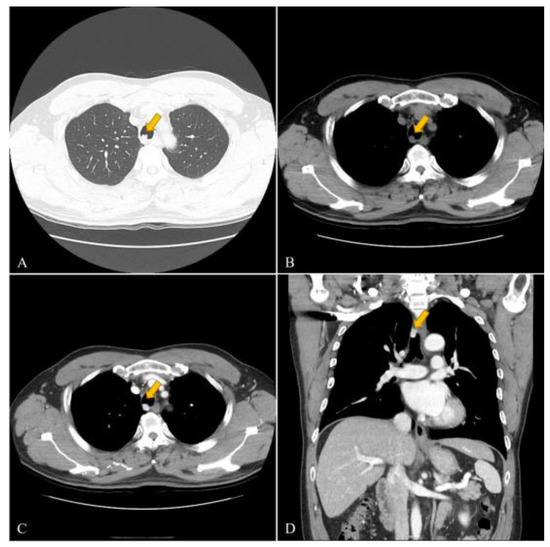

Tracheal Glomus Tumor: A Case Report with CT Imaging Features

2. Case Description